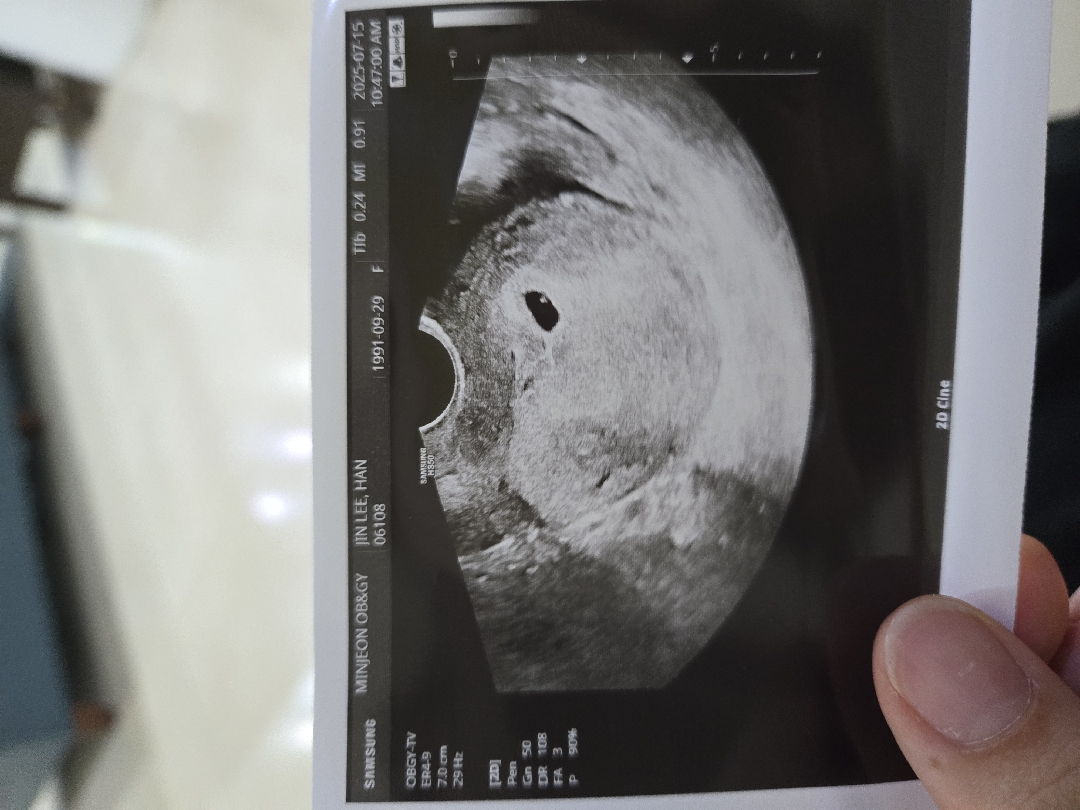

막생 6월 11일 이고 배란이 빨라서 4주 6일 예상하고갔는데 4주 5일 나오고 0.93으로 1센치 안돼는 아기집봤어요 너무 일찍 알아서 걱정했는데 안심이에요